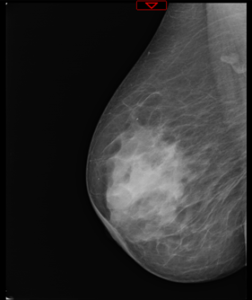

Mamografia

A mamografia é o melhor meio complementar de diagnóstico para a deteção do cancro da mama?

A mamografia é o melhor método de imagem para o diagnóstico de lesões palpáveis e impalpáveis da mama. É o único meio que permite a deteção precoce do cancro da mama. Deverá ser idealmente complementada com ecografia. A deteção de lesões suspeitas requer muitas vezes a utilização de diferentes técnicas, passando pela ecografia complementar da mamografia, até à ressonância magnética.

Atualmente, com os avanços tecnológicos, as técnicas de mamografia que utilizam os raios X têm uma elevada resolução e uma diminuição significativa da dose de radiação.

Cada mama é observada, pelo menos sob duas incidências, através do mamógrafo. Este aparelho é um equipamento de Raios-X, que faz incidir uma dose calculada e relativamente baixa de radiação sobre a mama, após compressão desta.